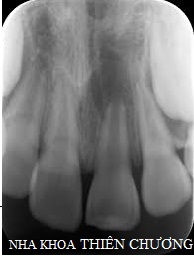

+ Chụp X-quang quanh chóp: đánh giá đối với một vùng răng cấn được                                     chẩn đoán bệnh để đưa ra kế hoạch điều trị chính xác.